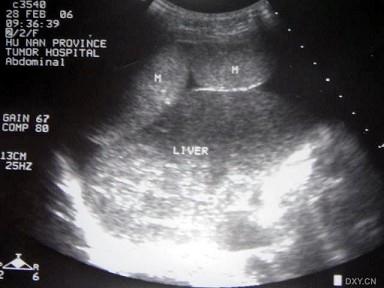

图中所示肿瘤最有可能是哪部位的占位?(?)A.肝脏B.腹膜C.肠道D.膈肌E.胰腺

问题 图中所示肿瘤最有可能是哪部位的占位?(?)

选项 A.肝脏 B.腹膜 C.肠道 D.膈肌 E.胰腺

答案 B